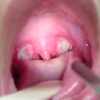

Νέα Υόρκη: Για παιδιά και ενήλικες που υποφέρουν συχνά από αμυγδαλίτιδα, η αφαίρεση των αμυγδαλών οδηγεί σε ουσιαστική βελτίωση της ποιότητας ζωής, σύμφωνα με δύο μελέτες που δημοσιεύονται στο Otolaryngology-Head and Neck Surgery.